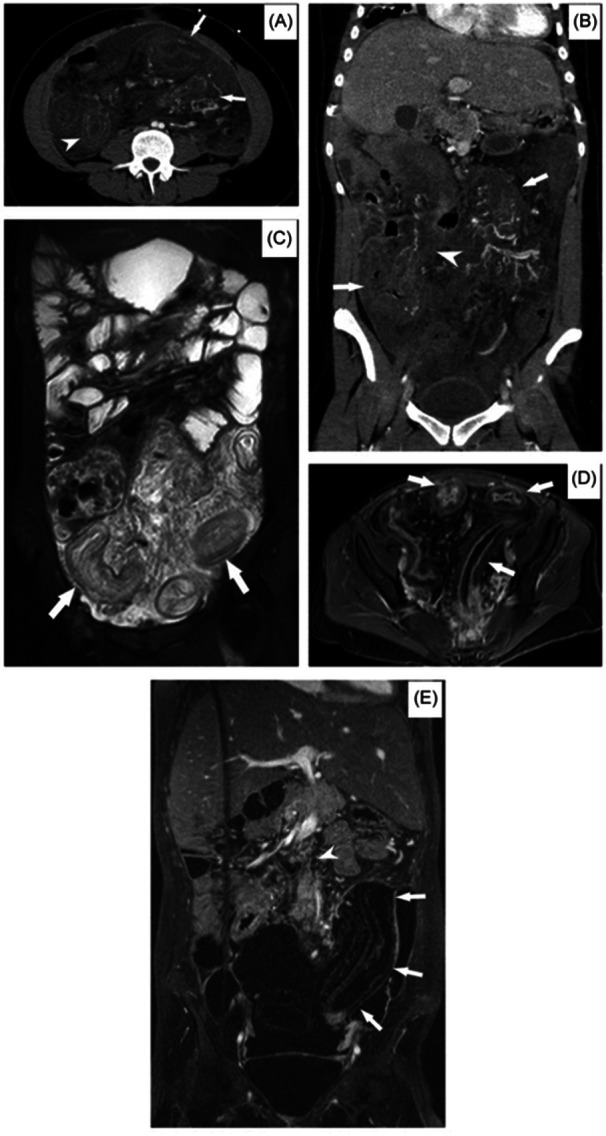

Idiopathic myointimal hyperplasia of the mesenteric veins (IMHMV) is a rare entity reported in adults, frequently mimicking inflammatory bowel disease (IBD). We report the first case of intestinal ischemia secondary to IMHMV presenting as IBD in a pediatric patient with Down syndrome. Chronic intestinal ischemia is rare in children, and this case emphasizes the need to consider this in the differential, when histopathology is suggestive. Clinical findings and colonoscopy in these patients may mimic IBD. The mucosal biopsies do not show classic features of IBD. Instead, there can be variable extent of mucosal changes such as dilated small capillaries in the lamina propria, edema, and early fibrosis. These changes may in fact represent early chronic ischemia. These findings should alert for vascular imaging and a full-thickness biopsy to assess submucosal and subserosal larger vessels since medium- and large-caliber veins in the colonic wall and mesentery are affected in IMHMV.